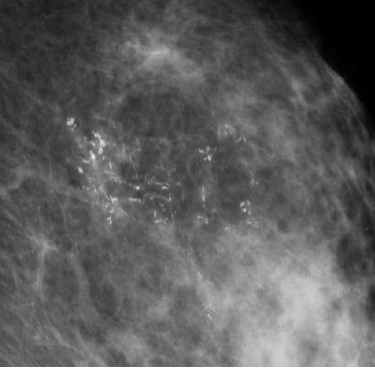

检查报告上出现“乳腺钙化灶”,特别是“成簇分布”、“形态不规则”时,很多女性的心都会揪紧。这些在钼靶片上如同细小白沙的砂砾可能是早期乳腺癌发出的唯一“求救信号”。如何精准探查这些深藏不露的砂砾”?这是乳腺钼靶(或称为乳腺X线)的独特价值,乳腺超声及乳腺磁共振无法取代。

2恶性钙化的“可疑特征”:

态: 细微、密度不均、形态不规则。可呈细沙样(细颗粒状)、小棒状(尤其分支状)、分叉状(像小树枝杈)。

分布:成簇聚集(单位面积内数量多)、呈段样或线样分布(提示沿导管蔓延),边界可能模糊。

联风险: 这种钙化模式常与乳腺导管内病变(如导管原位癌 )或某些浸润性癌相关,是早期癌变的重要影像学征象。

多形性钙化-颗粒点状钙化          线样分支状钙化